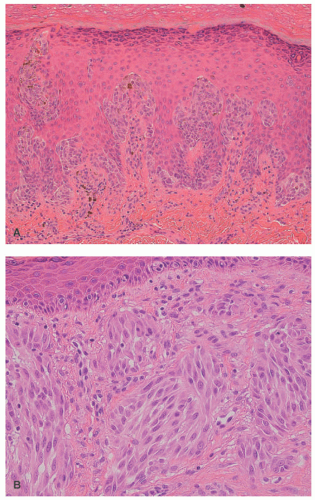

The following are some of the applied morphologic features of a ASNT: (1) lesions greater than 1 cm; (2) solid rather than nested growth pattern extending to the deep reticular dermis and into the subcutis with exceptions; (3) asymmetrical growth into dermis; and (4) cytologic atypia in the form of enlarged nuclei with pleomorphism and dense irregular chromatin.72,100 Nuclear atypia and its degree are subjective from one observer to another to account in part for the inter- and intraobserver variability. We have found it helpful to review the last “typical” SN and compare it to the current case where there is concern about an ASNT. Marked atypia is usually present throughout all levels of an ASNT, and mitotic figures, if present, should be counted with a threshold of greater or less than 6 mitoses per mm (Figure 22-18A and B).2 The emphasis on mitotic figures in the evaluation of any melanocytic lesion is usually focused upon those mitoses in the mid-to-deep reticular dermis. However, numerous mitotic figures wherever they are identified should be integrated into the overall assessment with the other histopathologic findings, which is the case in any nevocellular proliferation.